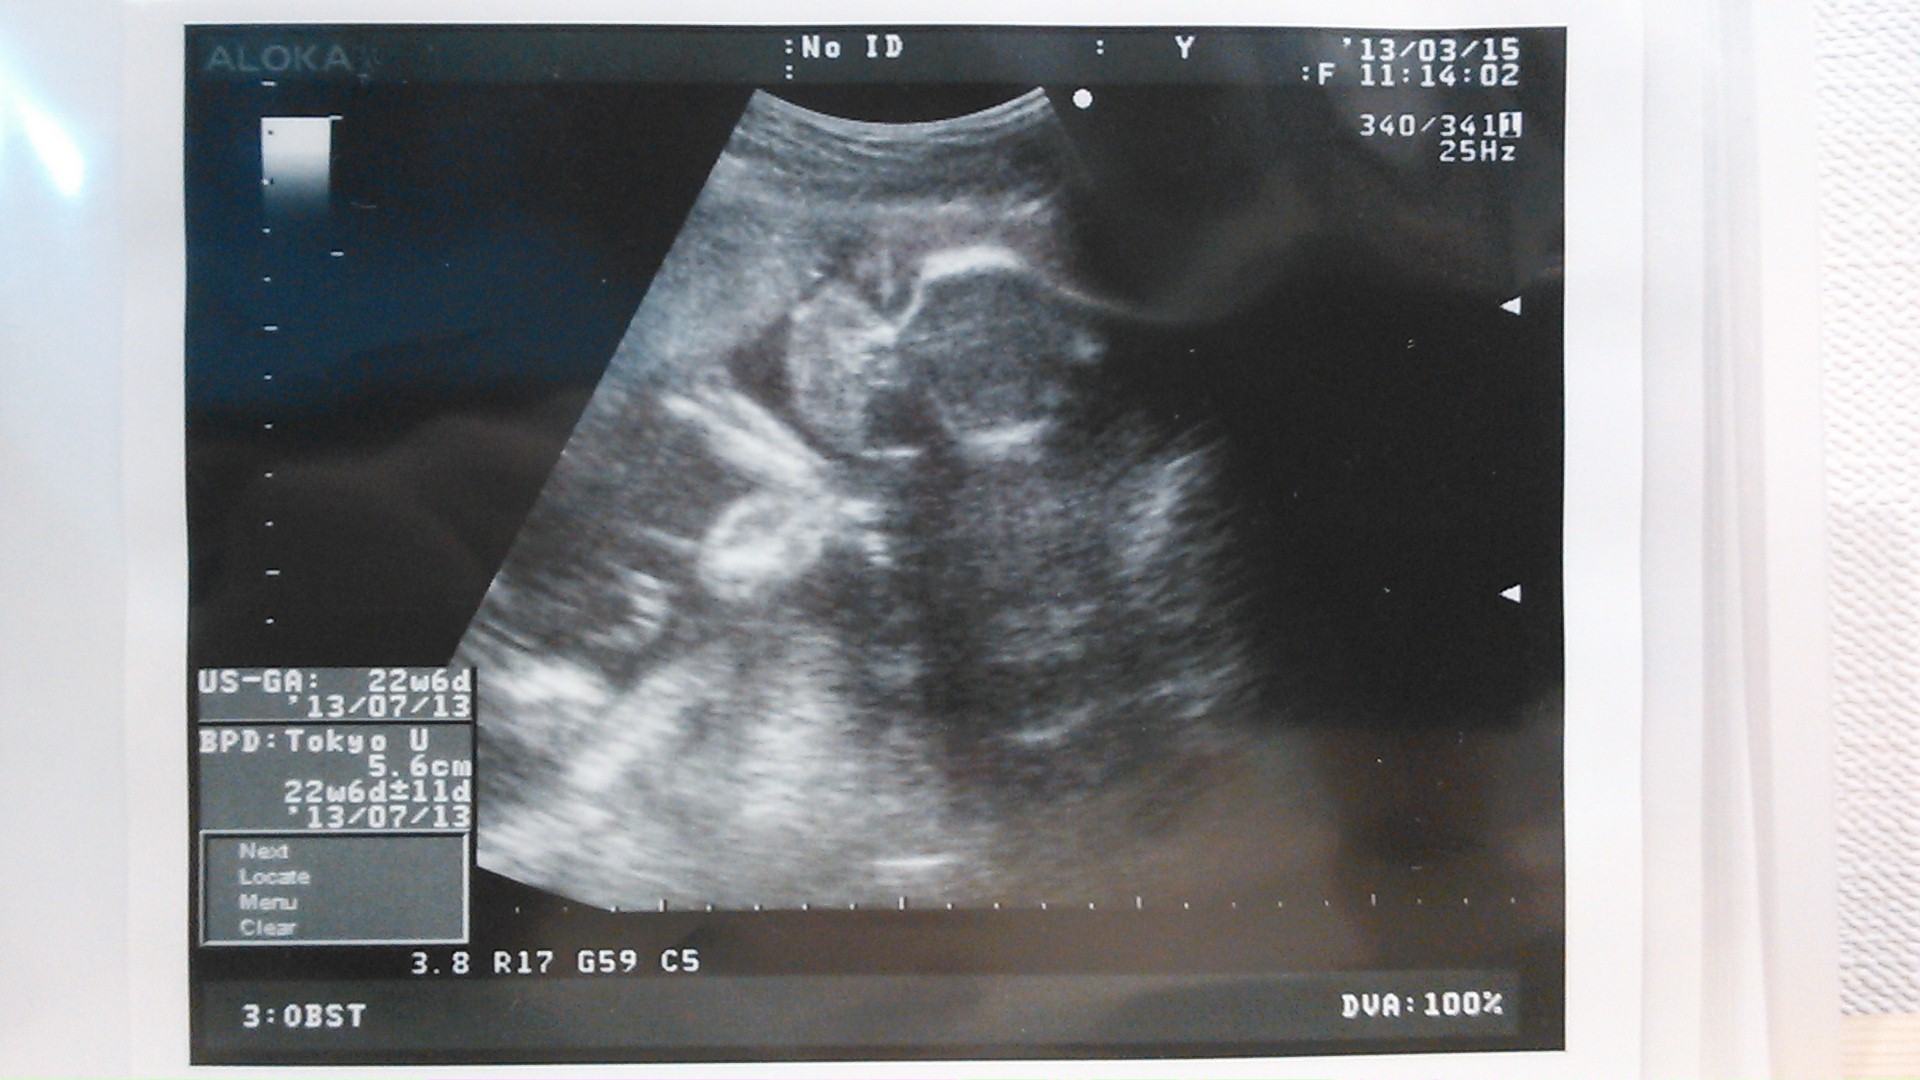

echo